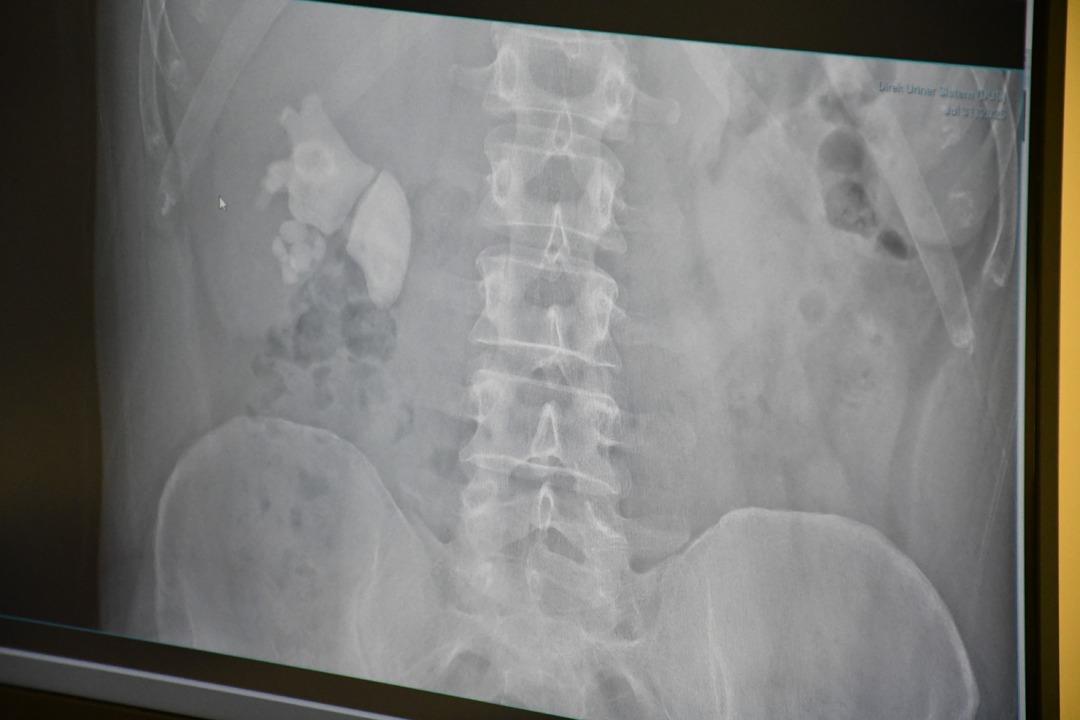

Kendilerini şiddetli böbrek ağrısı ile Yozgat şehrinin hastanesine uygulayan Evran'ın ayrıntılı sınavlarının ardından böbrekte yaklaşık 100 taş tespit edildi.

“Tamam böbrek taş doluydu”

Kamocanoglu, “Sağ böbrek incelememiz taşlarla doluydu. Hasta hastayla tanıştı ve bu kadar büyük taşlarda büyük bir ameliyat olabilir ve hasta bazı deliklere girdi, ameliyatın sırtını gerçekleştirerek yapılması gerektiğini söyledi. Hasta kabul etti. Hastanın müdahalesini Çarşamba günü yaptık.”